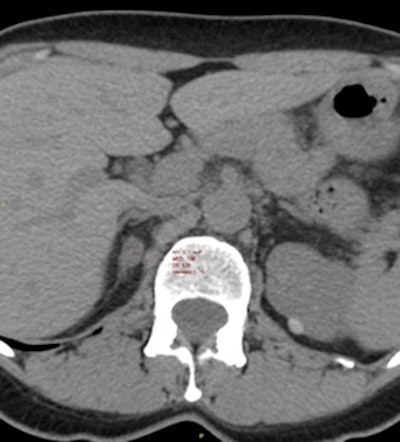

New research from Italy has highlighted how the use of CT is uncovering a growing number of incidental findings. About 4% of CT scans will detect a subclinical "silent" tumor in the adrenal gland, which presents a challenge due to inadequate information available about disease progression, according to the study authors.

Furthermore, with no letup in the demand for CT, detection of these adrenal incidentalomas looks set to increase, making it vital for doctors to formulate patient-tailored and cost-effective treatment plans.

The 15-year study, published online on 29 January in Lancet: Diabetes & Endocrinology, may prove the first step toward establishing an accepted treatment strategy tailored to each patient that, speculatively, will both improve their outcomes and optimize expenditure. It shows how such adrenal incidentalomas progress and how tumor type and progression can have an impact on patients' risk of cardiovascular (CV) event and death.